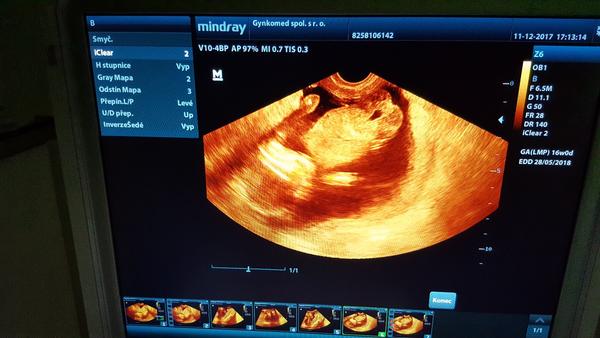

Je to holčička nebo chlapeček? Foto ultrazvuku

Ahoj maminky a budoucí maminky 😉 Prosím, poradila byste mi některá, co vidíte na fotce z ultrazvuku ve 20. týdnu za pohlaví? Určitě jste foteček viděly už mraky, proto vás žádám o radu...Nechci nikoho ovlivnit, proto svůj tip řeknu později 🙂 Děkuju moc!!!